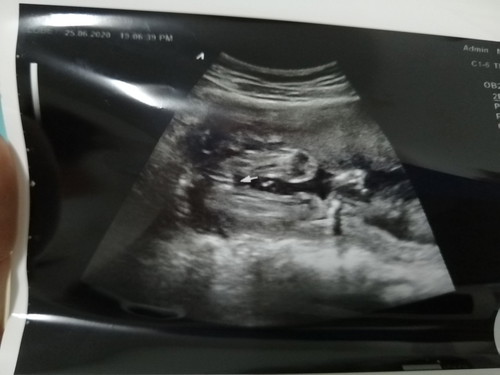

ได้ลูกสาว

ตอนนี้ท้องได้ 21w4d กำหนดคลอดวันที่ 3 พฤศจิกายน คะไปเซาดูเพศมาหมอบอกได้ลูกสาว99% ถูกใจคุณแม่มากคะ🥰